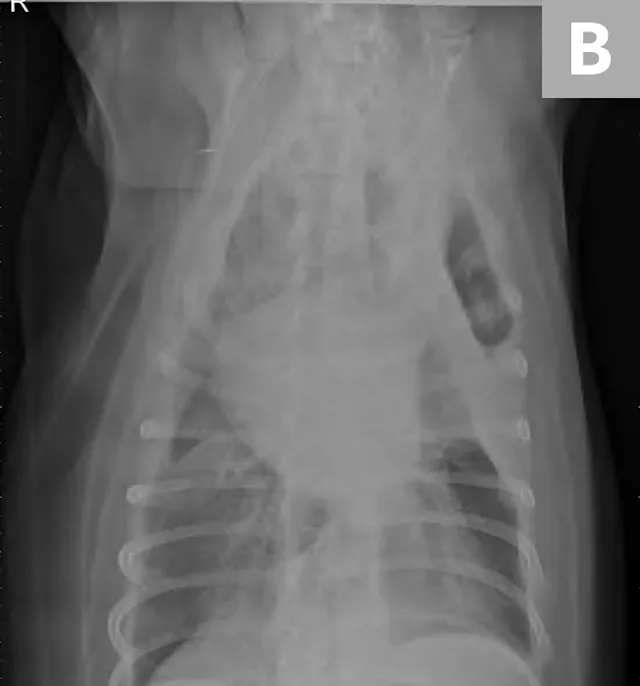

FIGURE 3A

Right lateral (A) and ventrodorsal (B) thoracic radiographs obtained after thoracocentesis showing improvement in pleural effusion with a persistent soft tissue opacity in the left mid-to-cranial thorax. An air bronchogram is seen extending cranially from the hilus (arrowhead) where a subtle bulge (arrow) is present.